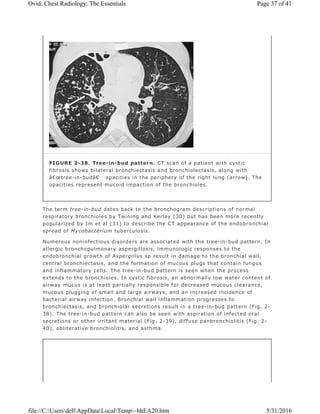

The term tree-in-bud dates back to the bronchogram descriptions of normal

respiratory bronchioles by Twining and Kerley (30) but has been more recently

popularized by Im et al (31) to describe the CT appearance of the endobronchial

spread of Mycobacterium tuberculosis.

Numerous noninfectious disorders are associated with the tree-in-bud pattern. In

allergic bronchopulmonary aspergillosis, immunologic responses to the

endobronchial growth of Aspergillus sp result in damage to the bronchial wall,

central bronchiectasis, and the formation of mucous plugs that contain fungus

and inflammatory cells. The tree-in-bud pattern is seen when the process

extends to the bronchioles. In cystic fibrosis, an abnormally low water content of

airway mucus is at least partially responsible for decreased mucous clearance,

mucous plugging of small and large airways, and an increased incidence of

bacterial airway infection. Bronchial wall inflammation progresses to

bronchiectasis, and bronchiolar secretions result in a tree-in-bud pattern (Fig. 2-

38). The tree-in-bud pattern can also be seen with aspiration of infected oral

secretions or other irritant material (Fig. 2-39), diffuse panbronchiolitis (Fig. 2-

40), obliterative bronchiolitis, and asthma.

FIGURE 2-38. Tree-in-bud pattern. CT scan of a patient with cystic

fibrosis shows bilateral bronchiectasis and bronchiolectasis, along with

“tree-in-bud†opacities in the periphery of the right lung (arrow). The

opacities represent mucoid impaction of the bronchioles.